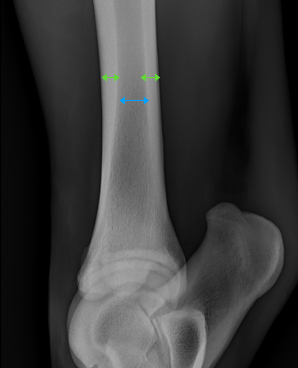

This image is of a normal tibia seen from the side of the horse. The structure of the long bone is well defined, with the denser cortical bone to the outside (appearing whiter) shown by the green lines, and less dense medullary bone on the inside (appearing greyer) shown by the blue line.